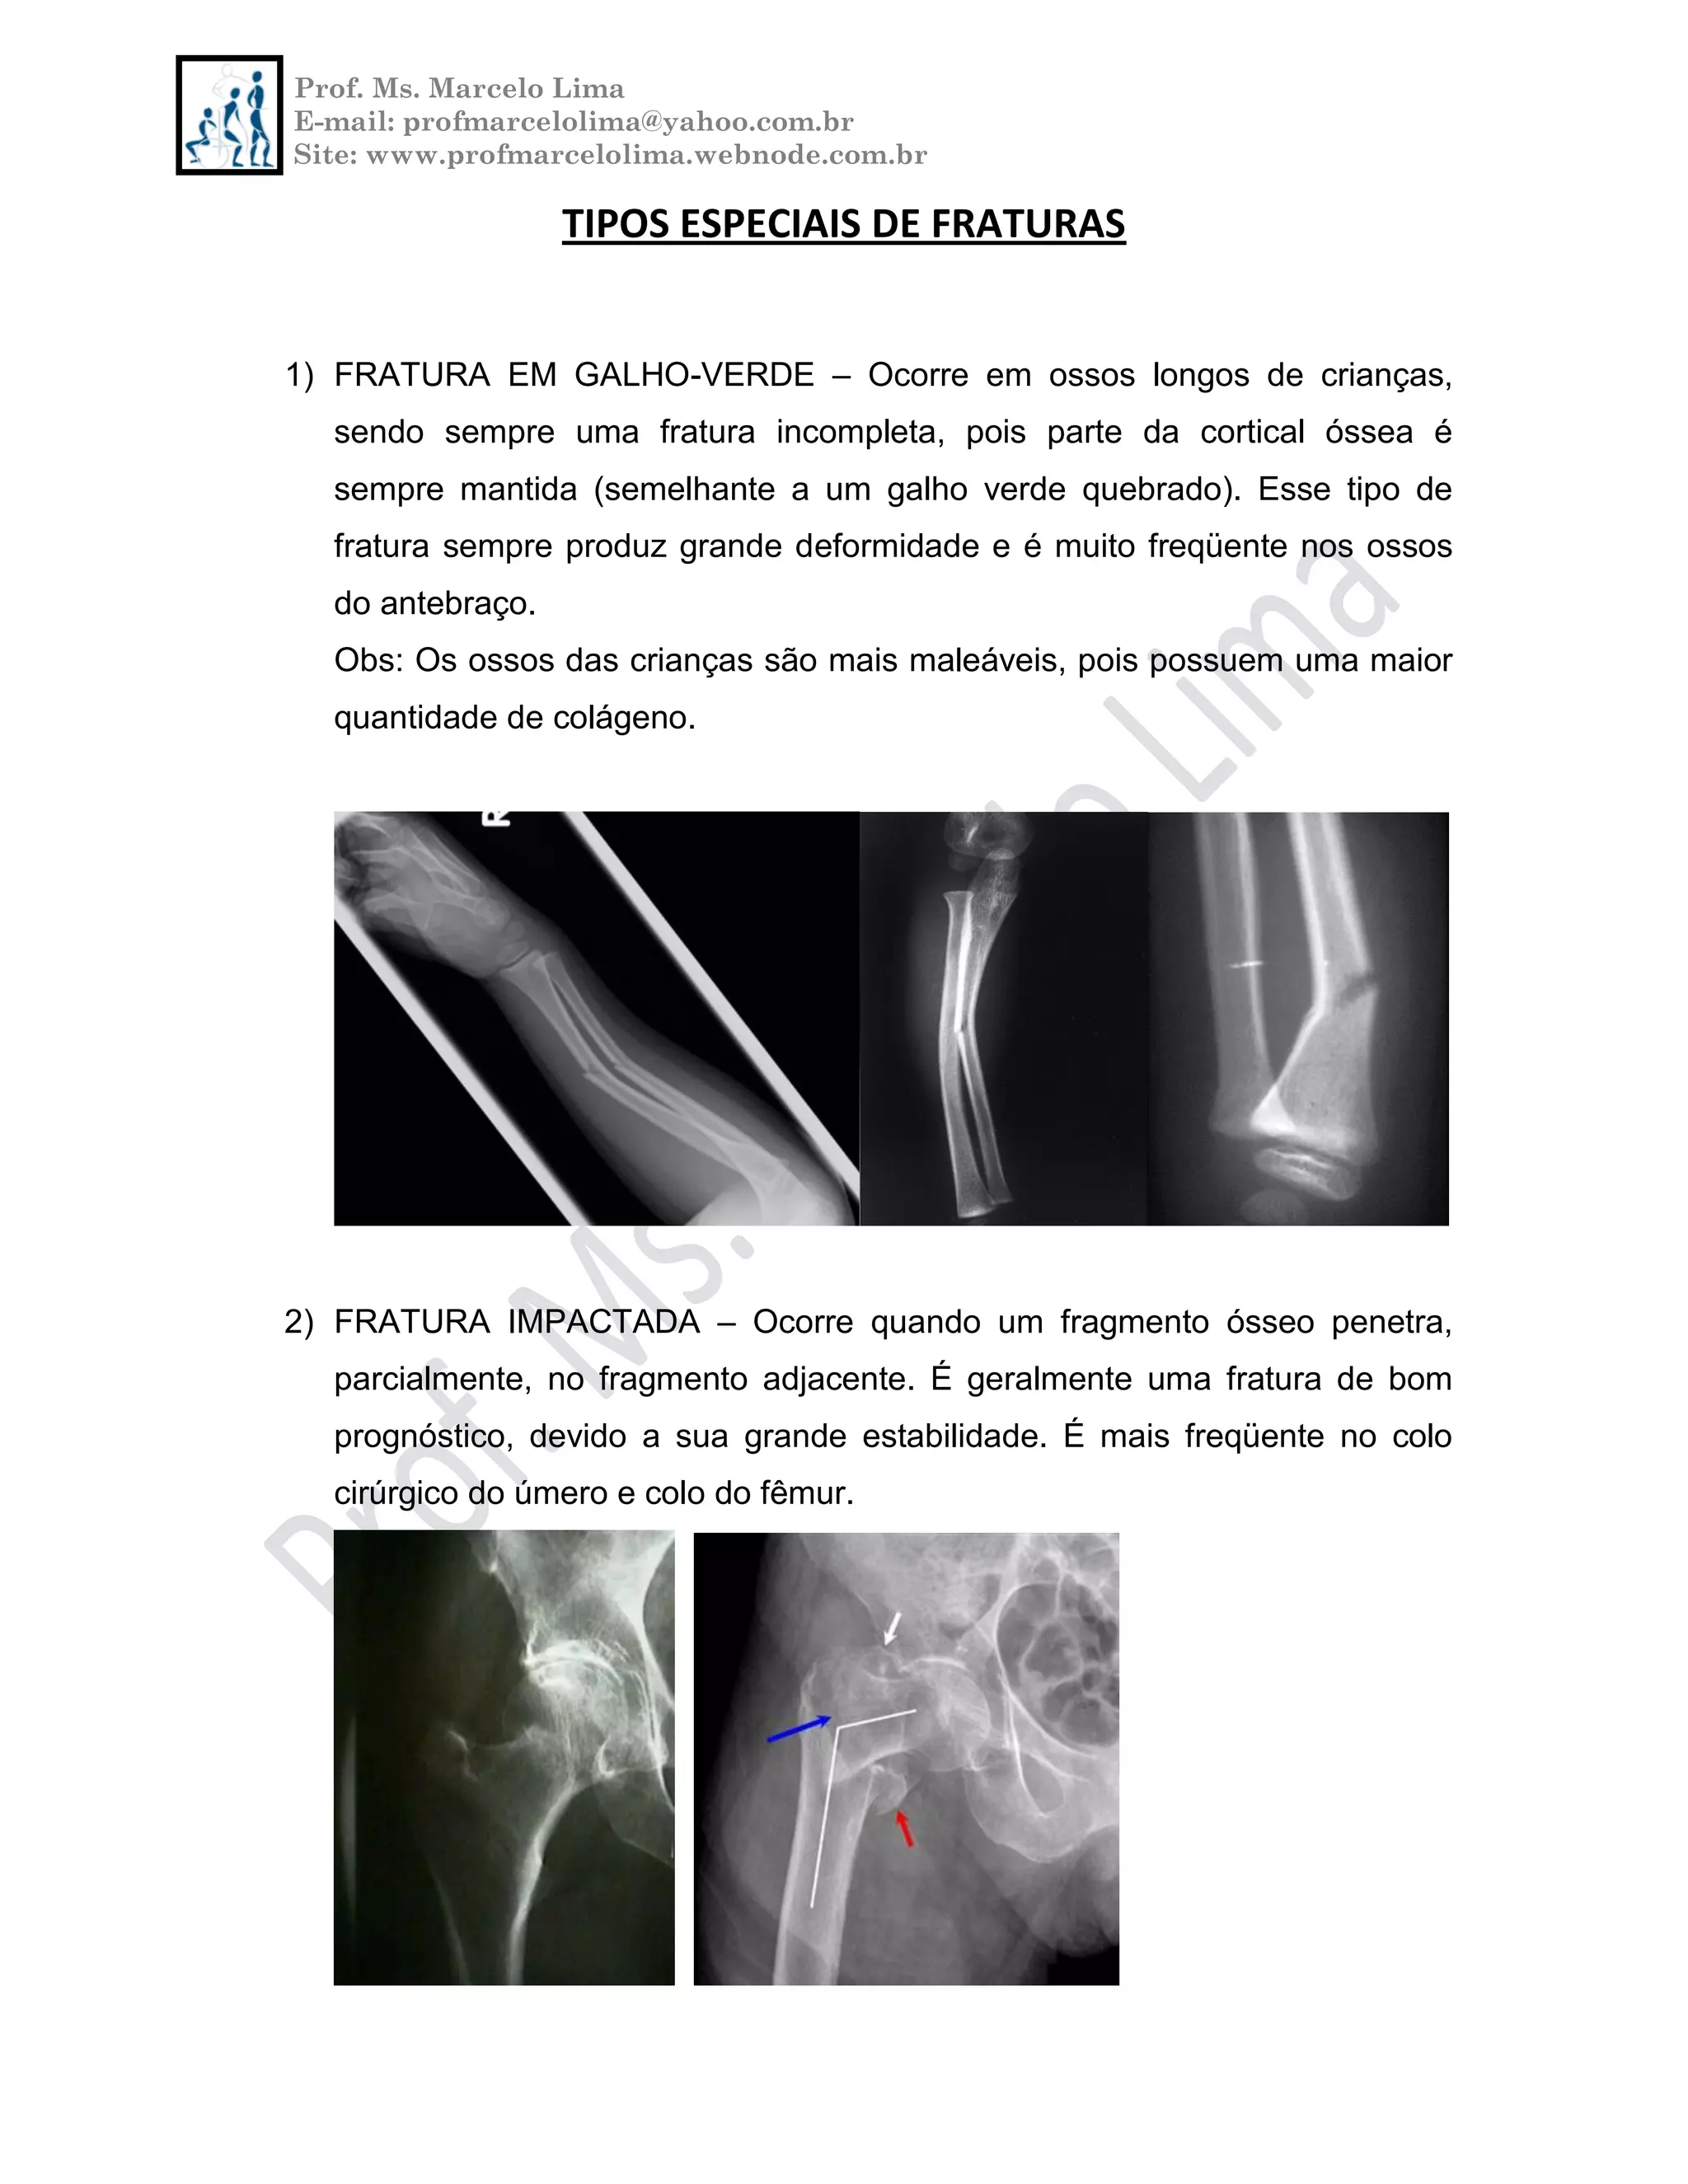

1) FRATURA EM GALHO-VERDE – Ocorre em ossos longos de crianças,

sendo sempre uma fratura incompleta, pois parte da cortical óssea é

sempre mantida (semelhante a um galho verde quebrado). Esse tipo de

fratura sempre produz grande deformidade e é muito freqüente nos ossos

do antebraço.

Obs: Os ossos das crianças são mais maleáveis, pois possuem uma maior

quantidade de colágeno.

2) FRATURA IMPACTADA – Ocorre quando um fragmento ósseo penetra,

parcialmente, no fragmento adjacente. É geralmente uma fratura de bom

prognóstico, devido a sua grande estabilidade. É mais freqüente no colo

cirúrgico do úmero e colo do fêmur.